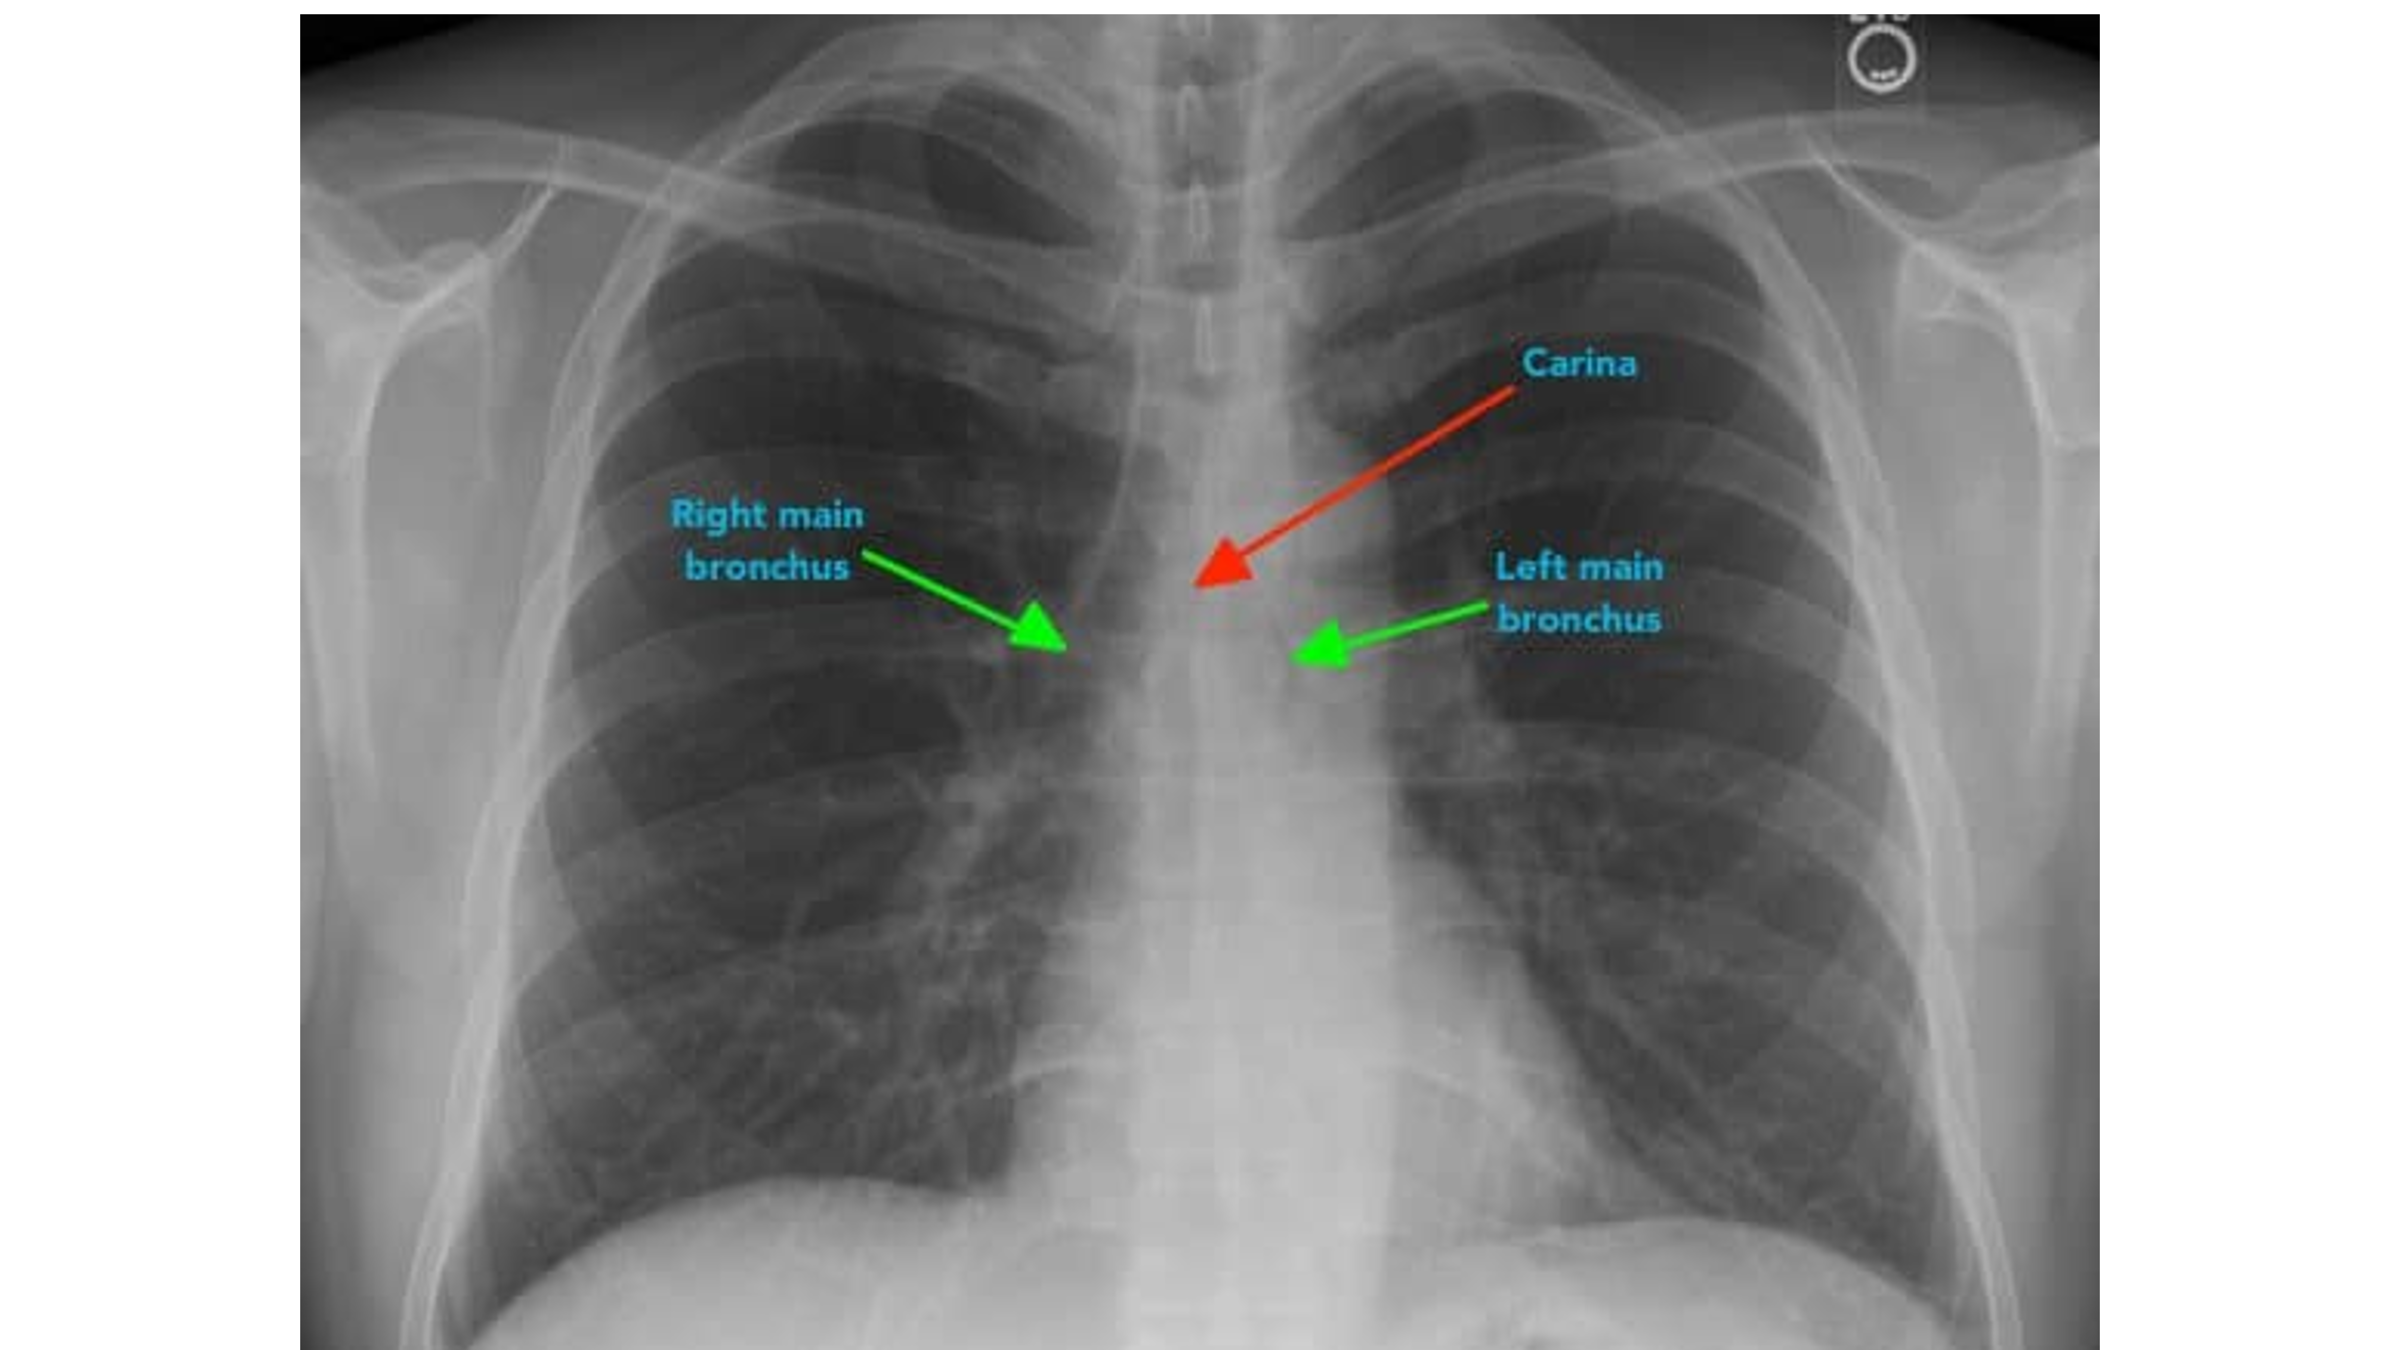

Airway (trachea, carina, bronchi, hilar structures)

Carina

NOTE: a correctly placed NG tube will bisect the carina

The ____ main bronchus is wider, shorter and more vertical than the ____ main bronchus.

right; left

It is more common for inhaled foreign objects to become lodged in the ____ main bronchus.

right